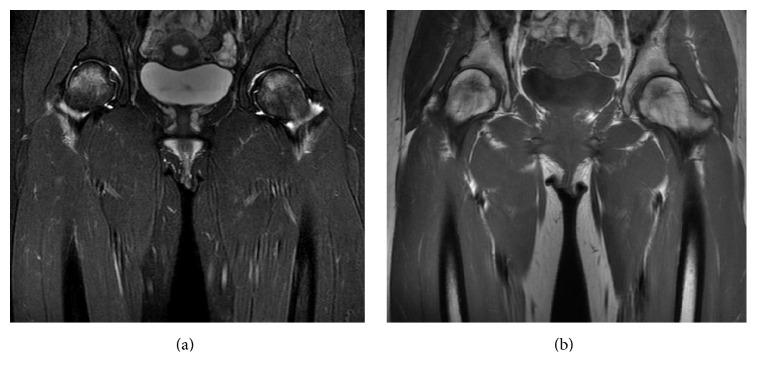

Transient osteoporosis of the hip (TOH) is a rare disorder characterized by acute severe coxalgia and temporary osteopenia in the proximal femur. Although most cases were unilateral or staged bilateral TOH, some authors reported that the pregnant patients simultaneously had TOH in their bilateral hips. However, there has been no report of simultaneous bilateral TOH in the patient without pregnancy. A 25-year-old Japanese woman without pregnancy had acute simultaneous bilateral hip pain. Plain X-ray of the bilateral hips did not show a periarticular osteopenia. However, magnetic resonance image obtained one week after the onset demonstrated increased T2-weighted signal intensity and decreased T1-weighted signal intensity in the bilateral femoral heads. She was treated conservatively, and follow-up magnetic resonance image at seven weeks after the onset returned to normal bone marrow signal intensity. Her bilateral coxalgia subsided gradually. At one year after the onset, she had no sign of symptomatic flair. Our experience with this case indicates that recognizing the possibility of simultaneous bilateral TOH is important unless the patient is pregnant, and magnetic resonance image is predictable test to make a diagnosis of TOH, even in the absence of abnormal finding on plain X-ray.

髋部短暂性骨质疏松症(TOH)是一种罕见的疾病,其特征为急性严重髋关节疼痛以及股骨近端暂时出现骨质减少。尽管大多数病例为单侧或分期双侧TOH,但一些作者报告称,孕妇双侧髋部会同时出现TOH。然而,尚无非妊娠患者双侧同时发生TOH的报告。一名25岁未怀孕的日本女性突发双侧髋部同时疼痛。双侧髋部的X线平片未显示关节周围骨质减少。然而,发病一周后获得的磁共振成像显示双侧股骨头T2加权信号强度增加,T1加权信号强度降低。她接受了保守治疗,发病七周后的随访磁共振成像显示骨髓信号强度恢复正常。她双侧髋关节疼痛逐渐缓解。发病一年后,她没有症状复发的迹象。我们对该病例的经验表明,除非患者怀孕,认识到双侧同时发生TOH的可能性很重要,而且即使X线平片无异常发现,磁共振成像也是诊断TOH的可预测性检查。